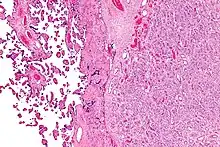

| Placenta with an especially large 10cm chorioangioma | |

Chorioangioma, or chorangioma, is a benign tumor of placenta. It is a hamartoma-like growth in the placenta consisting of blood vessels,[1] and is seen in approximately 0.5 to 1% pregnancies.[2] It is mostly diagnosed ultrasonically in the second trimester of pregnancy. Large chorioangiomas are known to cause complications in pregnancy, while the smaller ones are asymptomatic.

Histologically, chorioangiomas consist of abundant vascular channels and may be cellular.